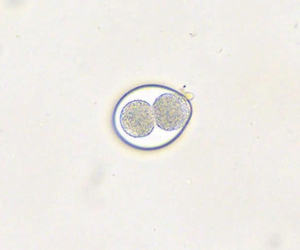

Hakenwürmer

Befallen: Hunde und Katzen jeden Alters

Mögliche Symptome: Dunkler, teerähnlicher Kot, Blutarmut und Durchfall

Zoonose: Infektion möglich